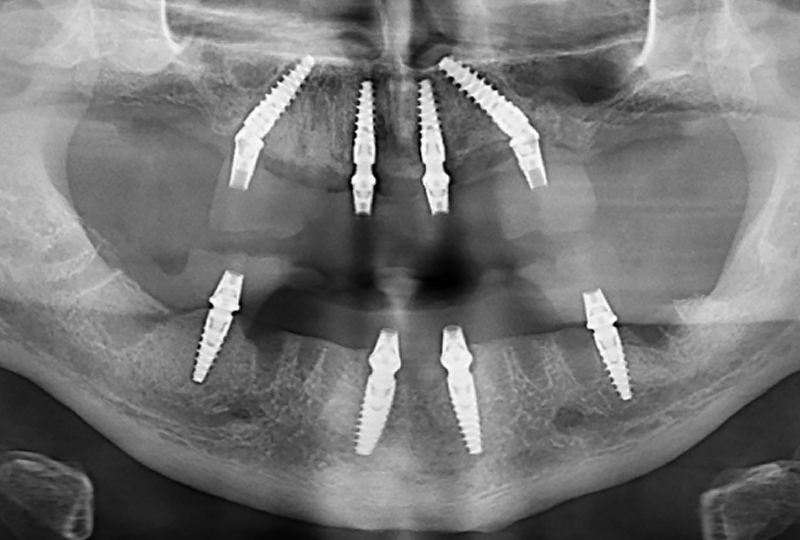

La proposta protesica fu una riabilitazione fissa supportata da impianti sia per l’arcata superiore che per quella inferiore, attraverso tecnica All-on 4. Prima della fase chirurgica, in un unico appuntamento, venivano acquisite le foto extra-orali in posizione di riposo, con un sorriso appena accennato, il massimo sorriso possibile, la CBCT delle arcate (ProMax 3D® Planmeca), le scansioni orali (TRIOS® 3, 3Shape) e le scansioni facciali (POP-2®, Revopoint) con un repere di posizionamento, in posizione di riposo e massimo sorriso. Con queste informazioni era possibile procedere, attraverso due sessioni di chirurgia eseguite secondo la tecnica All-on-4, al posizionamento di due protesi fisse a carico immediato in PMMA (Ceramill A-temp®, Amann Girrbach) (Figure 3,4).

A circa tre mesi dal secondo intervento si procedeva alla realizzazione delle protesi definitive in zirconia integrale. Come già sottolineato, il work flow digitale per la realizzazione dei definitivi prevedeva una serie di tre appuntamenti. Durante il primo di questi venivano rilevate nuove foto extra-orali (Figure 5,6,7) e scansioni intraorali (TRIOS® 3, 3Shape) (Figure 8,9,10).